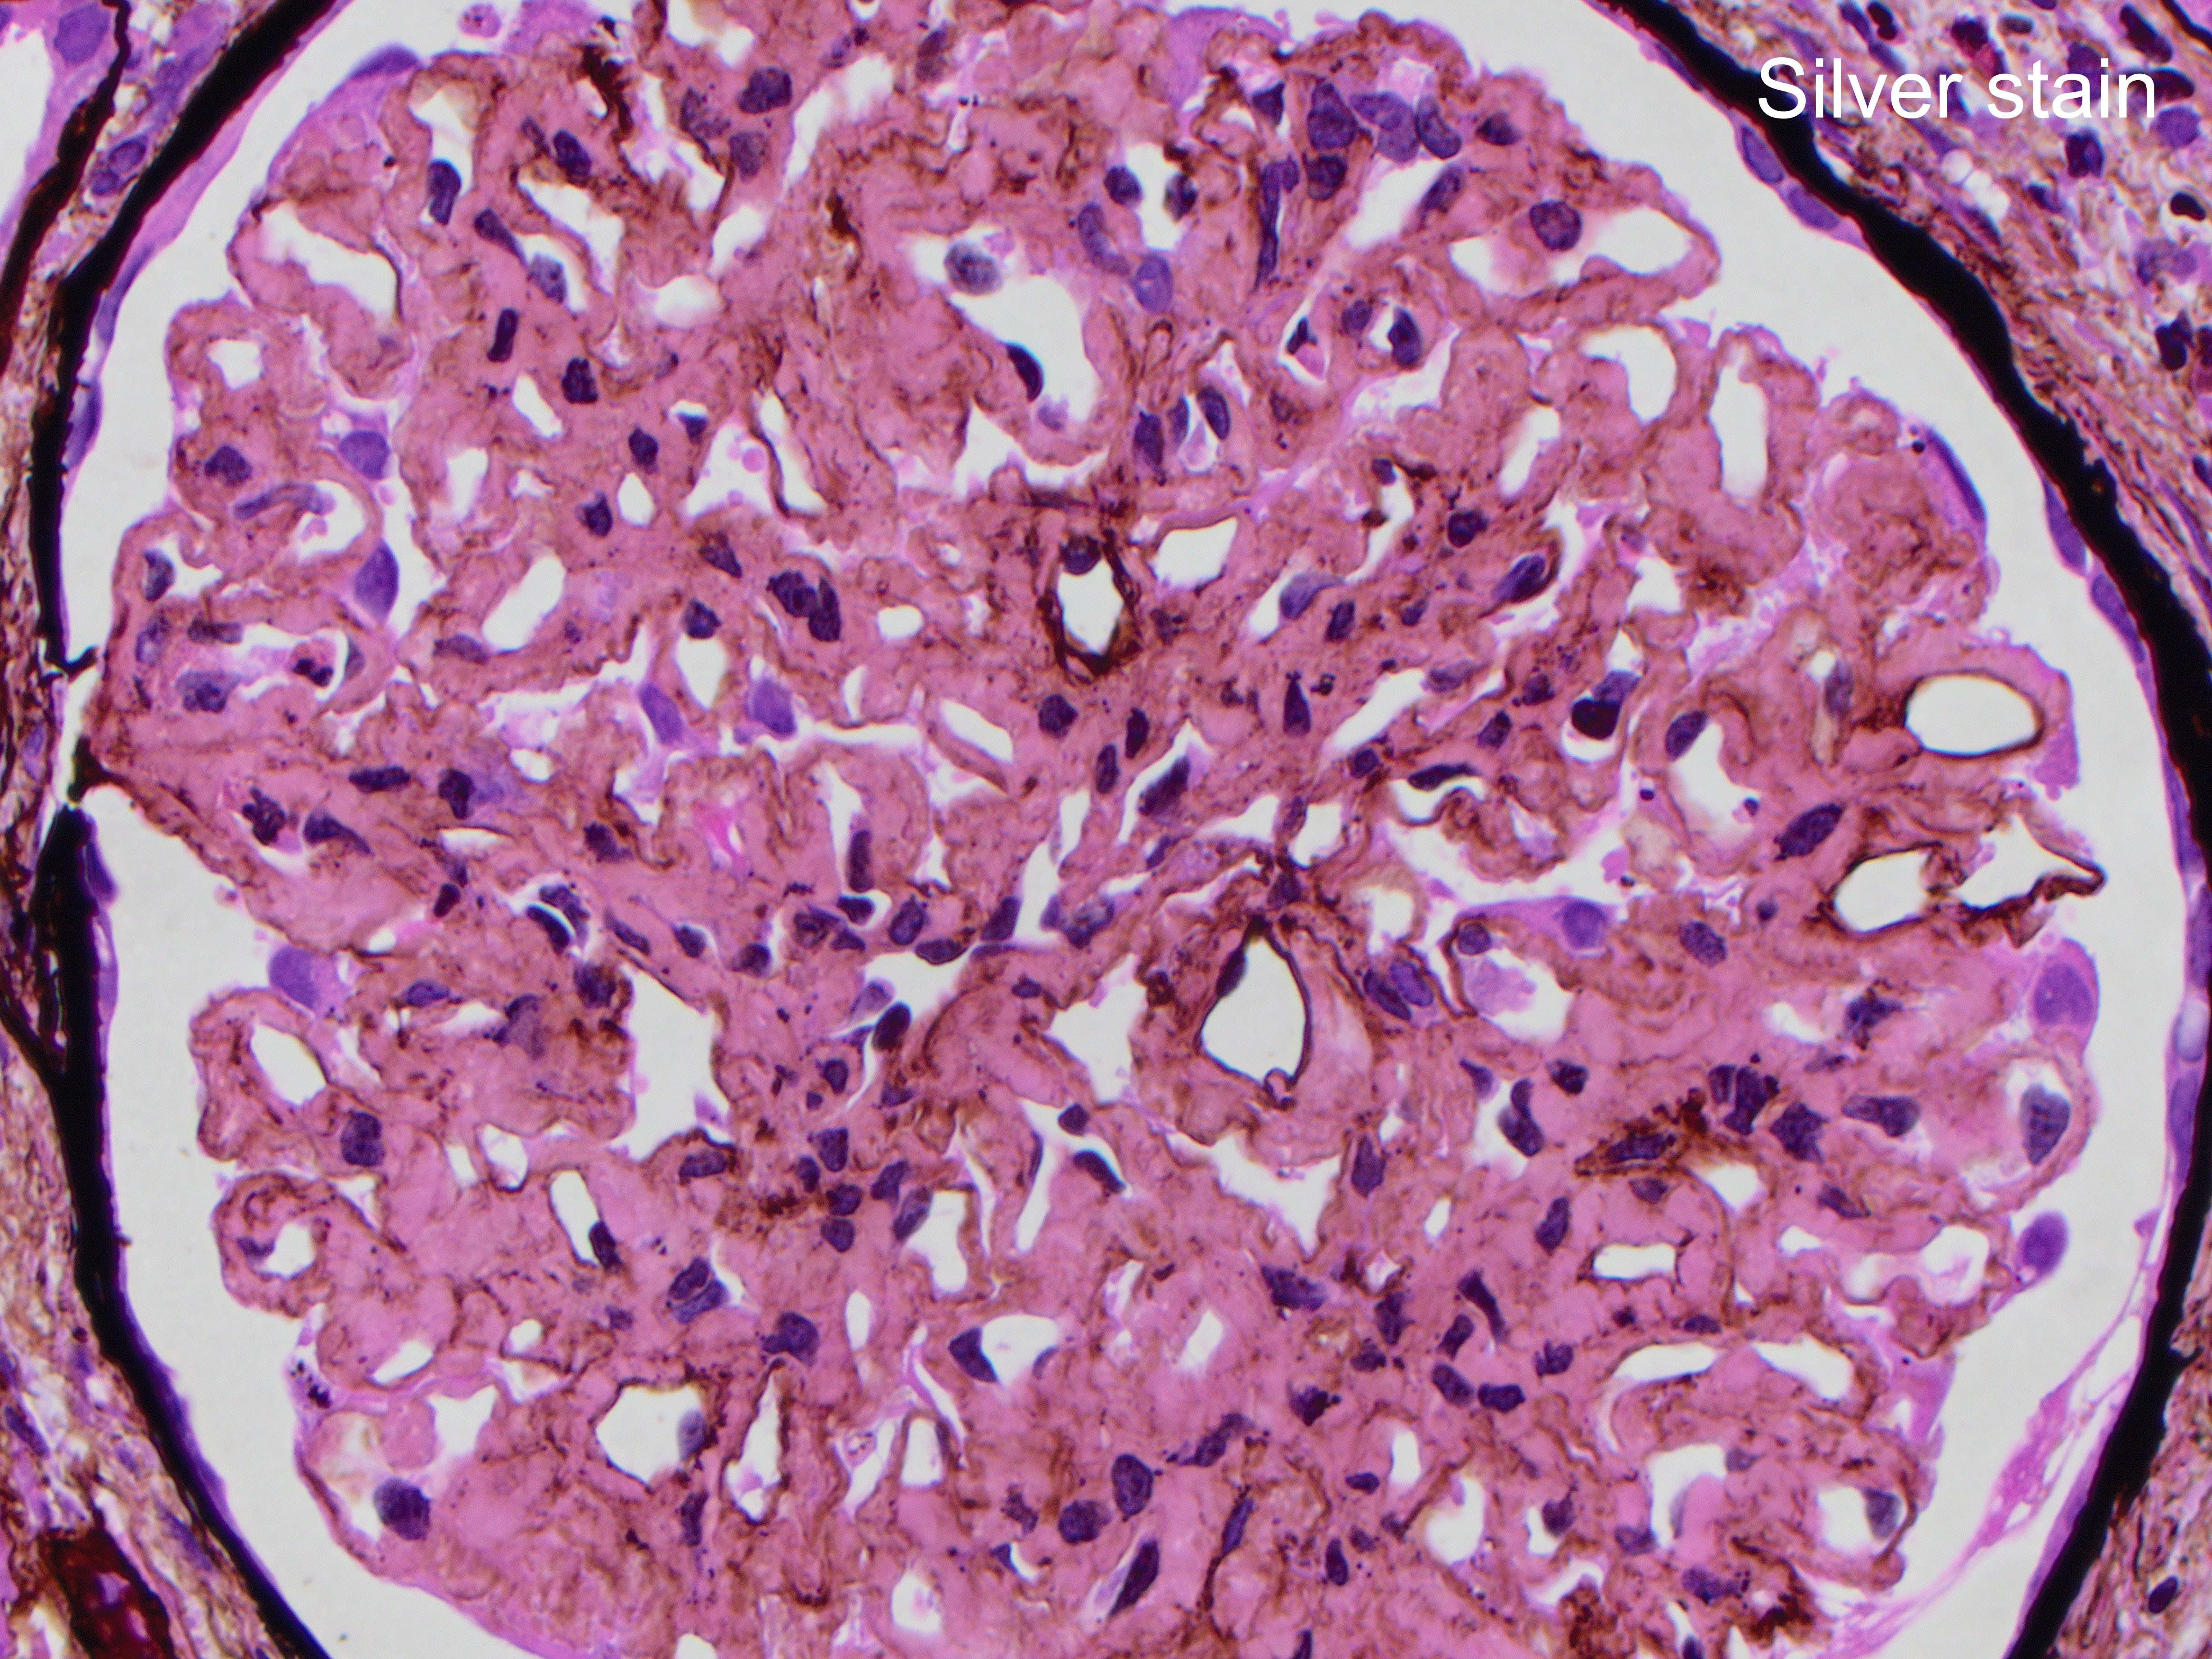

The patient is 32 year-old female with acute kidney injury and nephrotic range proteinuria. A renal biopsy showed diffuse global mesangial and capillary wall expansion by eosinophilic weakly PASH positive material (Silver stain showed in Figure 1), with cellular crescents in 40% and fibrocellular crescents in 5% of the glomeruli. A Congo red stain failed to show apple-green birefringence under polarized light (Figure 2). There was intense immunofluorescence staining with IgG, IgA, C3, and light chains (Figure 3). Electron microscopy showed fibrils with 25 nm average diameter (Figure 4).

By light microscopy, the most commonly reported patterns of injury are membranoproliferative and mesangial proliferative, with focal crescents in 17-50% of the cases (like in this case which showed less than 50% of glomeruli involved; figure). The deposits result in expansion of the mesangium and/or capillary walls by eosinophilic material that is pale with periodic acid-Schiff, nonargyrophilic, and negative for Congo red. By immunofluorescence, “smudgy” mesangial and/or capillary wall intense staining for IgG (most often IgG4 subclass), usually with C3, kappa and lambda light chains is noted. IgM, IgA and C1q show weaker positive staining in some cases.